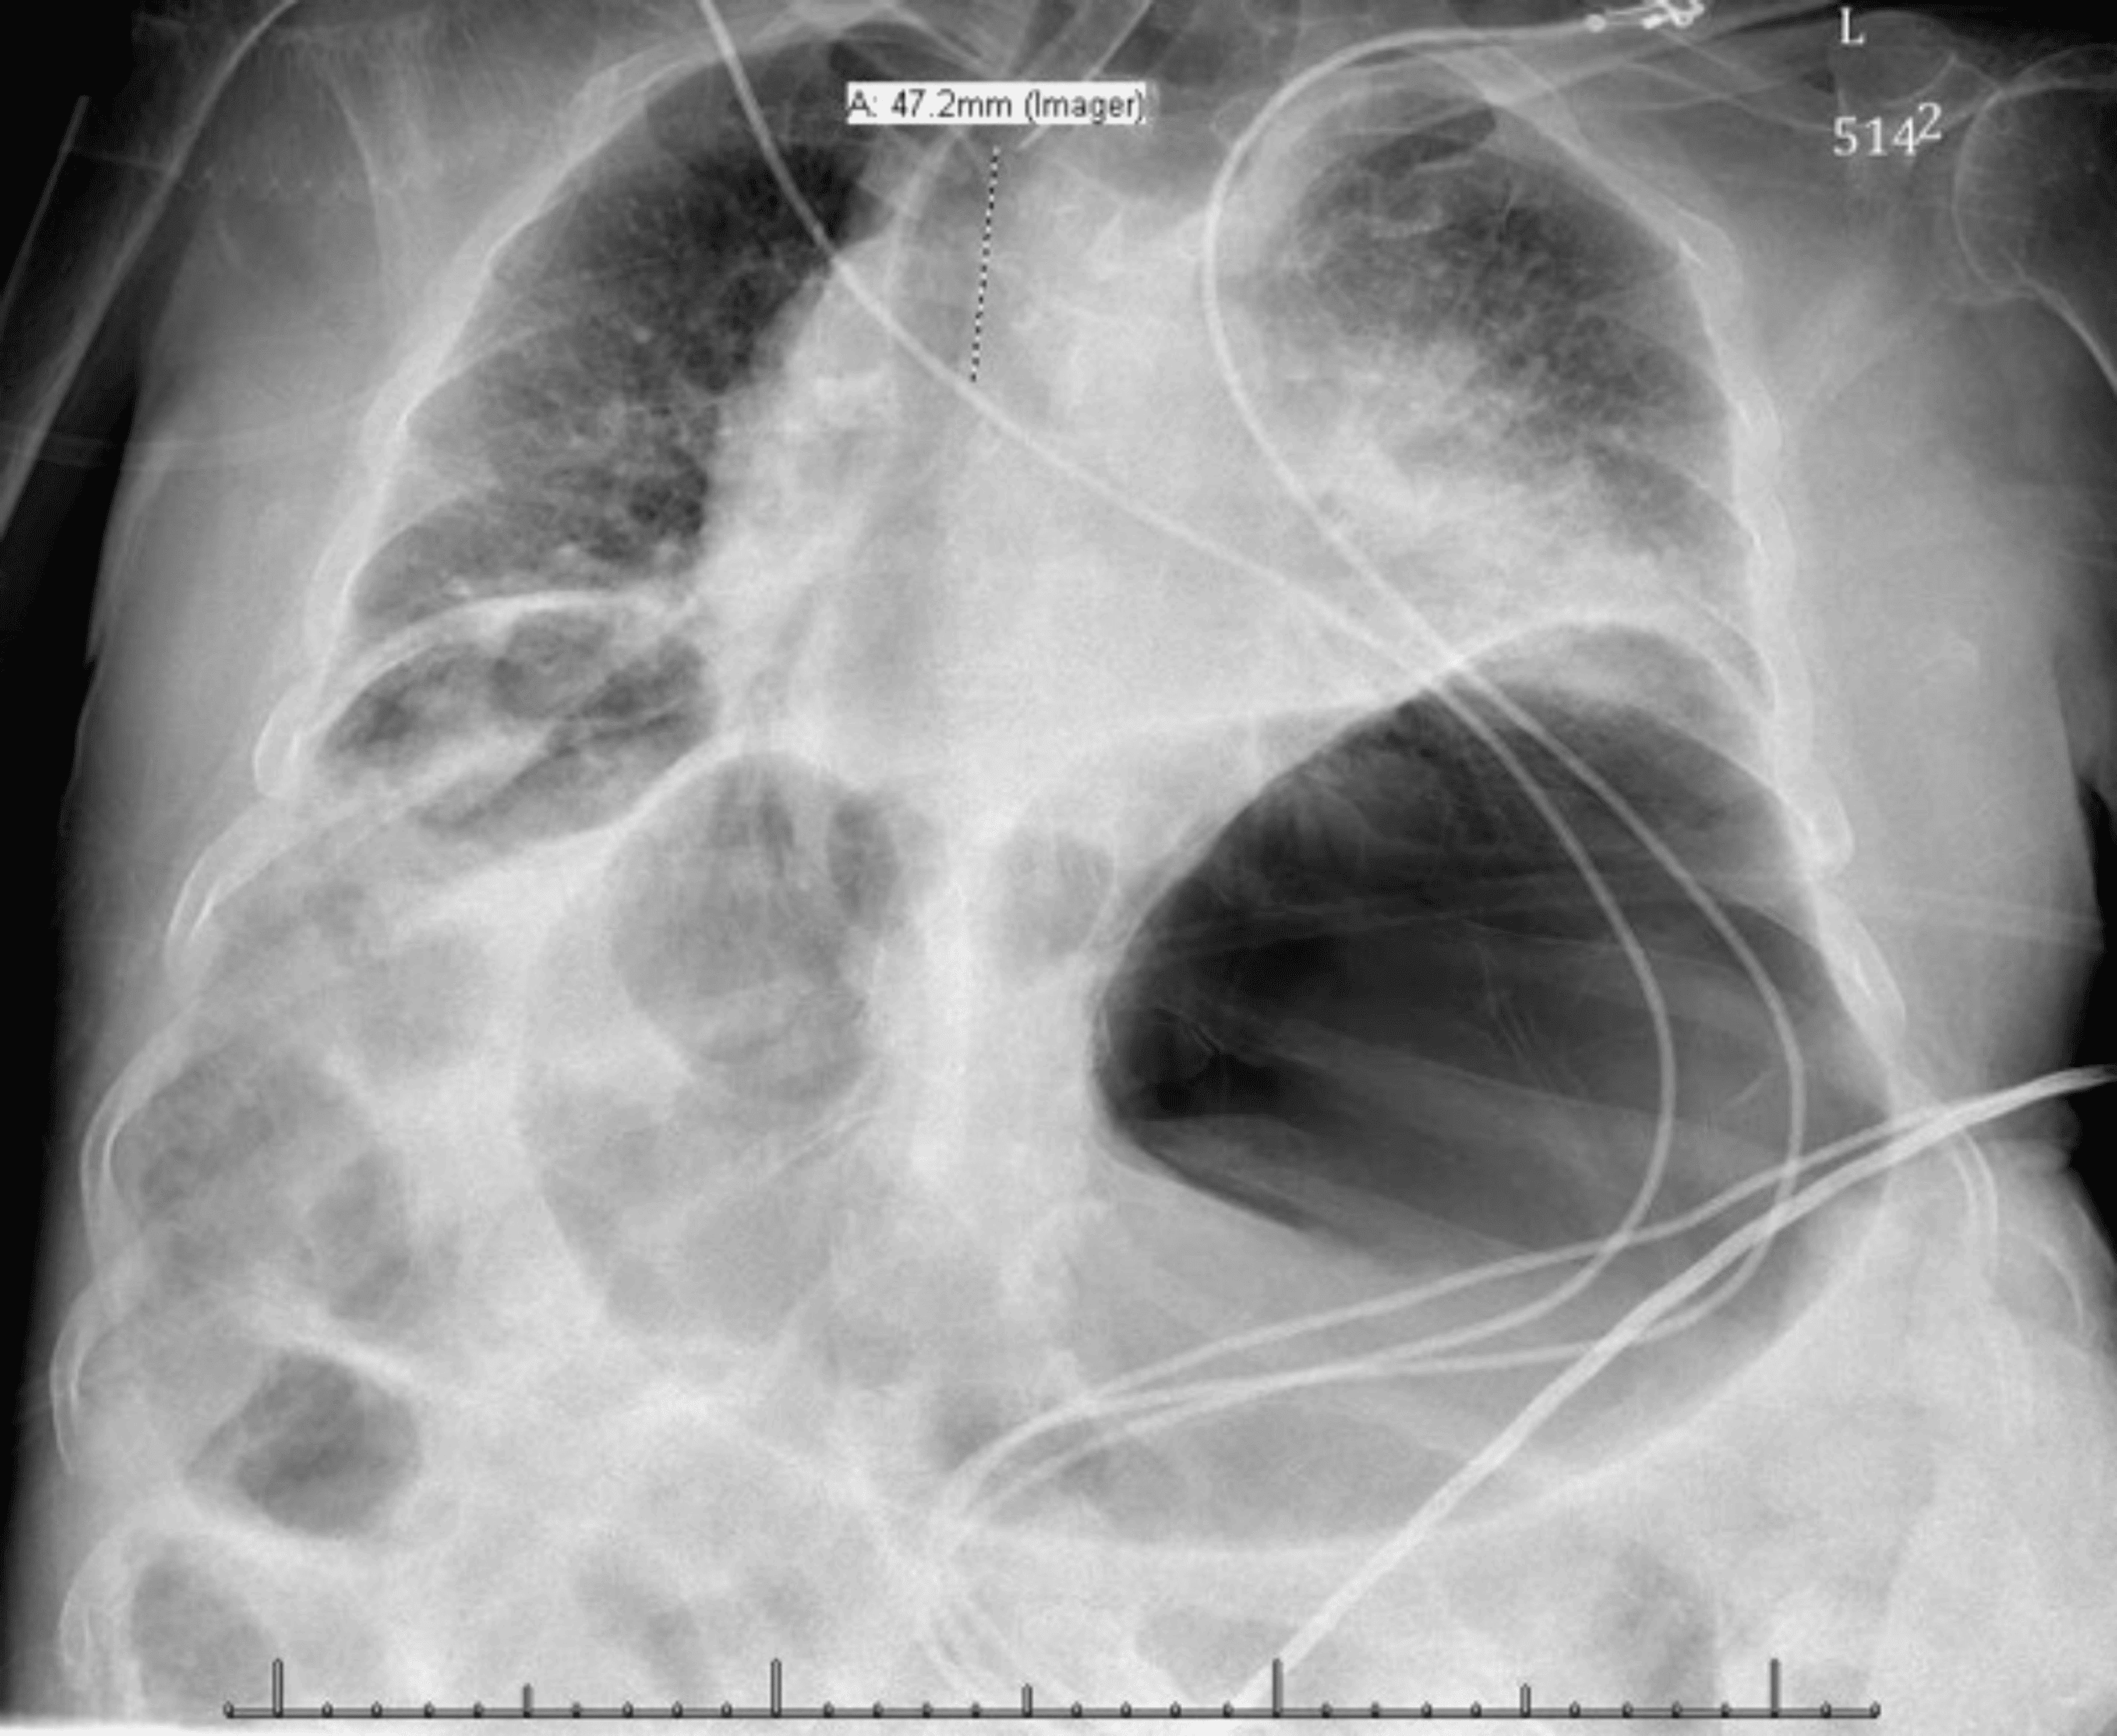

Chest Xray showed dextrocardia and rightsided gastric air bubble Chest X Ray Gastric Bubble The gastric bubble location was noted as (1). Fluid level or food contents. the gastric bubble is a radiolucent rounded area generally nestled under the left hemidiaphragm representing gas in the. The chest radiograph is performed for a broad content of indications, including but not limited to. Gas is also normally seen within the large. Gastric bubble is present. Chest X Ray Gastric Bubble.

Chest Xray image showing dextrocardia and a right subphrenic gastric Chest X Ray Gastric Bubble Gastric bubble is present in approximately 70% of normal chest and abdominal radiograph. The chest radiograph is performed for a broad content of indications, including but not limited to. the gastric bubble is a radiolucent rounded area generally nestled under the left hemidiaphragm representing gas in the. the appearance of the stomach bubble provides many clues to underlying. Chest X Ray Gastric Bubble.